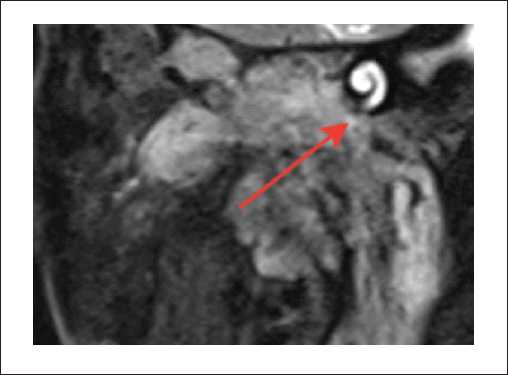

Пациенты третьей группы с диагностированной распространенной параганглиомой предъявляли жалобы на отсутствие слуха с пораженной стороны, периодическое онемение лица, периодические эпизоды кровотечения из слухового прохода. У 6 пациентов, которые до поступления в нашу клинику неоднократно подвергались хирургическим вмешательствам, отмечался парез лицевого нерва со стороны поражения, который соответствовал 5–6 степени по шкале House – Brackmann. При отоскопии у пациентов определялось выпирающее в просвет наружного слухового прохода красно-бордовое пульсирующее объемное образование. По данным лучевых исследований, на КТ височных костей у пациентов определялся мягкотканный субстрат, заполняющий барабанную полость. Крыша барабанной полости была истончена, местами не определялась (1). Костная стенка канала внутренней сонной артерии не прослеживалась. На уровне луковицы яремной вены определялось мягкотканное образование, которое разрушало костные стенки гипотимпанума (2) (рисунок 5).

Рисунок 5. КТ правой височной кости, аксиальная проекция. Параганглиома, тип С: задняя стенка нижнечелюстной ямки местами не определяется (1). На уровне яремной ямки определяется мягкотканное содержимое, которое разрушает костные стенки гипотимпанума (2).

На МРТ головного мозга и мягких тканей шеи определялось распространение образования на капсулу улитки и на область правой мостомозжечковой цистерны (рисунки 6, 8, 9). Соответствующие отделы головного мозга не изменены. Определялись признаки распространения процесса по ходу внутренней яремной вены (1). Просвет внутренней яремной вены в этой области не прослеживался (2) (рисунок 7).